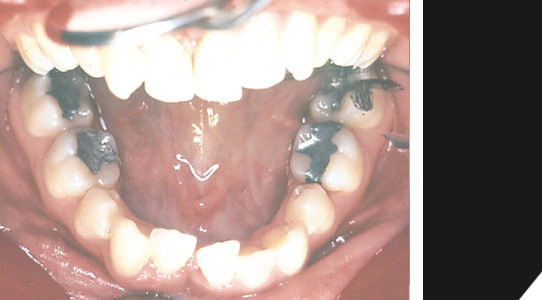

Der selbe Patient nach der erfolgreichen Behandlung, mit harmonisch ausgeformter Zahnreihe. Die Kieferfehlstellung im Unter- und Oberkieferbereich wurde behoben. Die Schneidezähne im oberen Bereich sind wieder gerade.

Hier noch ein Vorher- / Nachherfall, bei dem sogenannte Brackets eingesetzt werden.